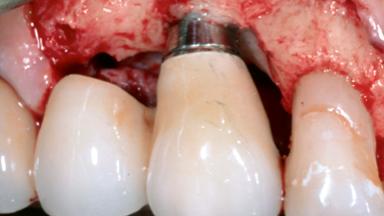

A 79-year-old female patient was referred to the Department of Periodontology of the University of Bern, Switzerland by her private dentist in May 2019. She had been rehabilitated in May 2005 with two tissue-level implants (Institut Straumann AG, Basel Switzerland) at sites 13 and 15, supporting a three-unit cemented fixed dental prosthesis (FDP). The metal-ceramic FDP had been cemented permanently with a glass-ionomer cement (Ketac Cem; 3M ESPE, Seefeld, Germany). Implant 13 had been diagnosed with peri-implant mucositis by the referring dentist in the course of regular supportive therapy. The patient was in good general health, did not smoke, and exhibited good self-performed plaque control.